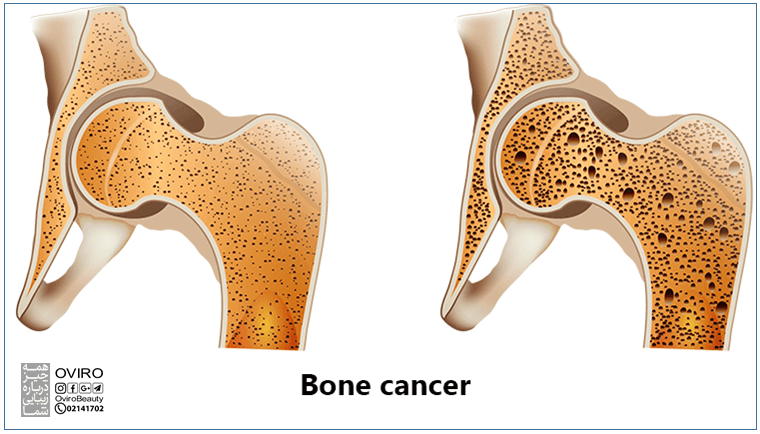

در برخی موارد سرطان می تواند یک استخوان را ضعیف کرده و باعث شکستگی ساده تر آن در اثر آسیب دیدگی جزئی یا افتادن شود.